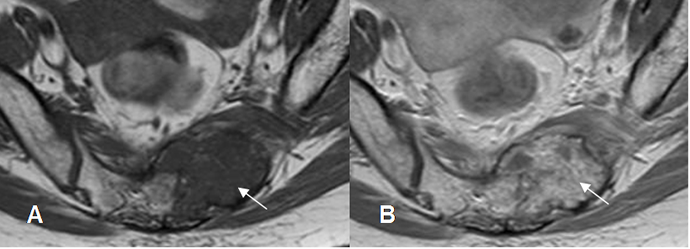

Fig 10. Realce del contraste.

A: RM axial en T1 simple y B: RM axial en T1 con contraste. Lesión hipointensa en el alerón izquierdo del sacro, que realza con el contraste, por metástasis de neoplasia del colon.